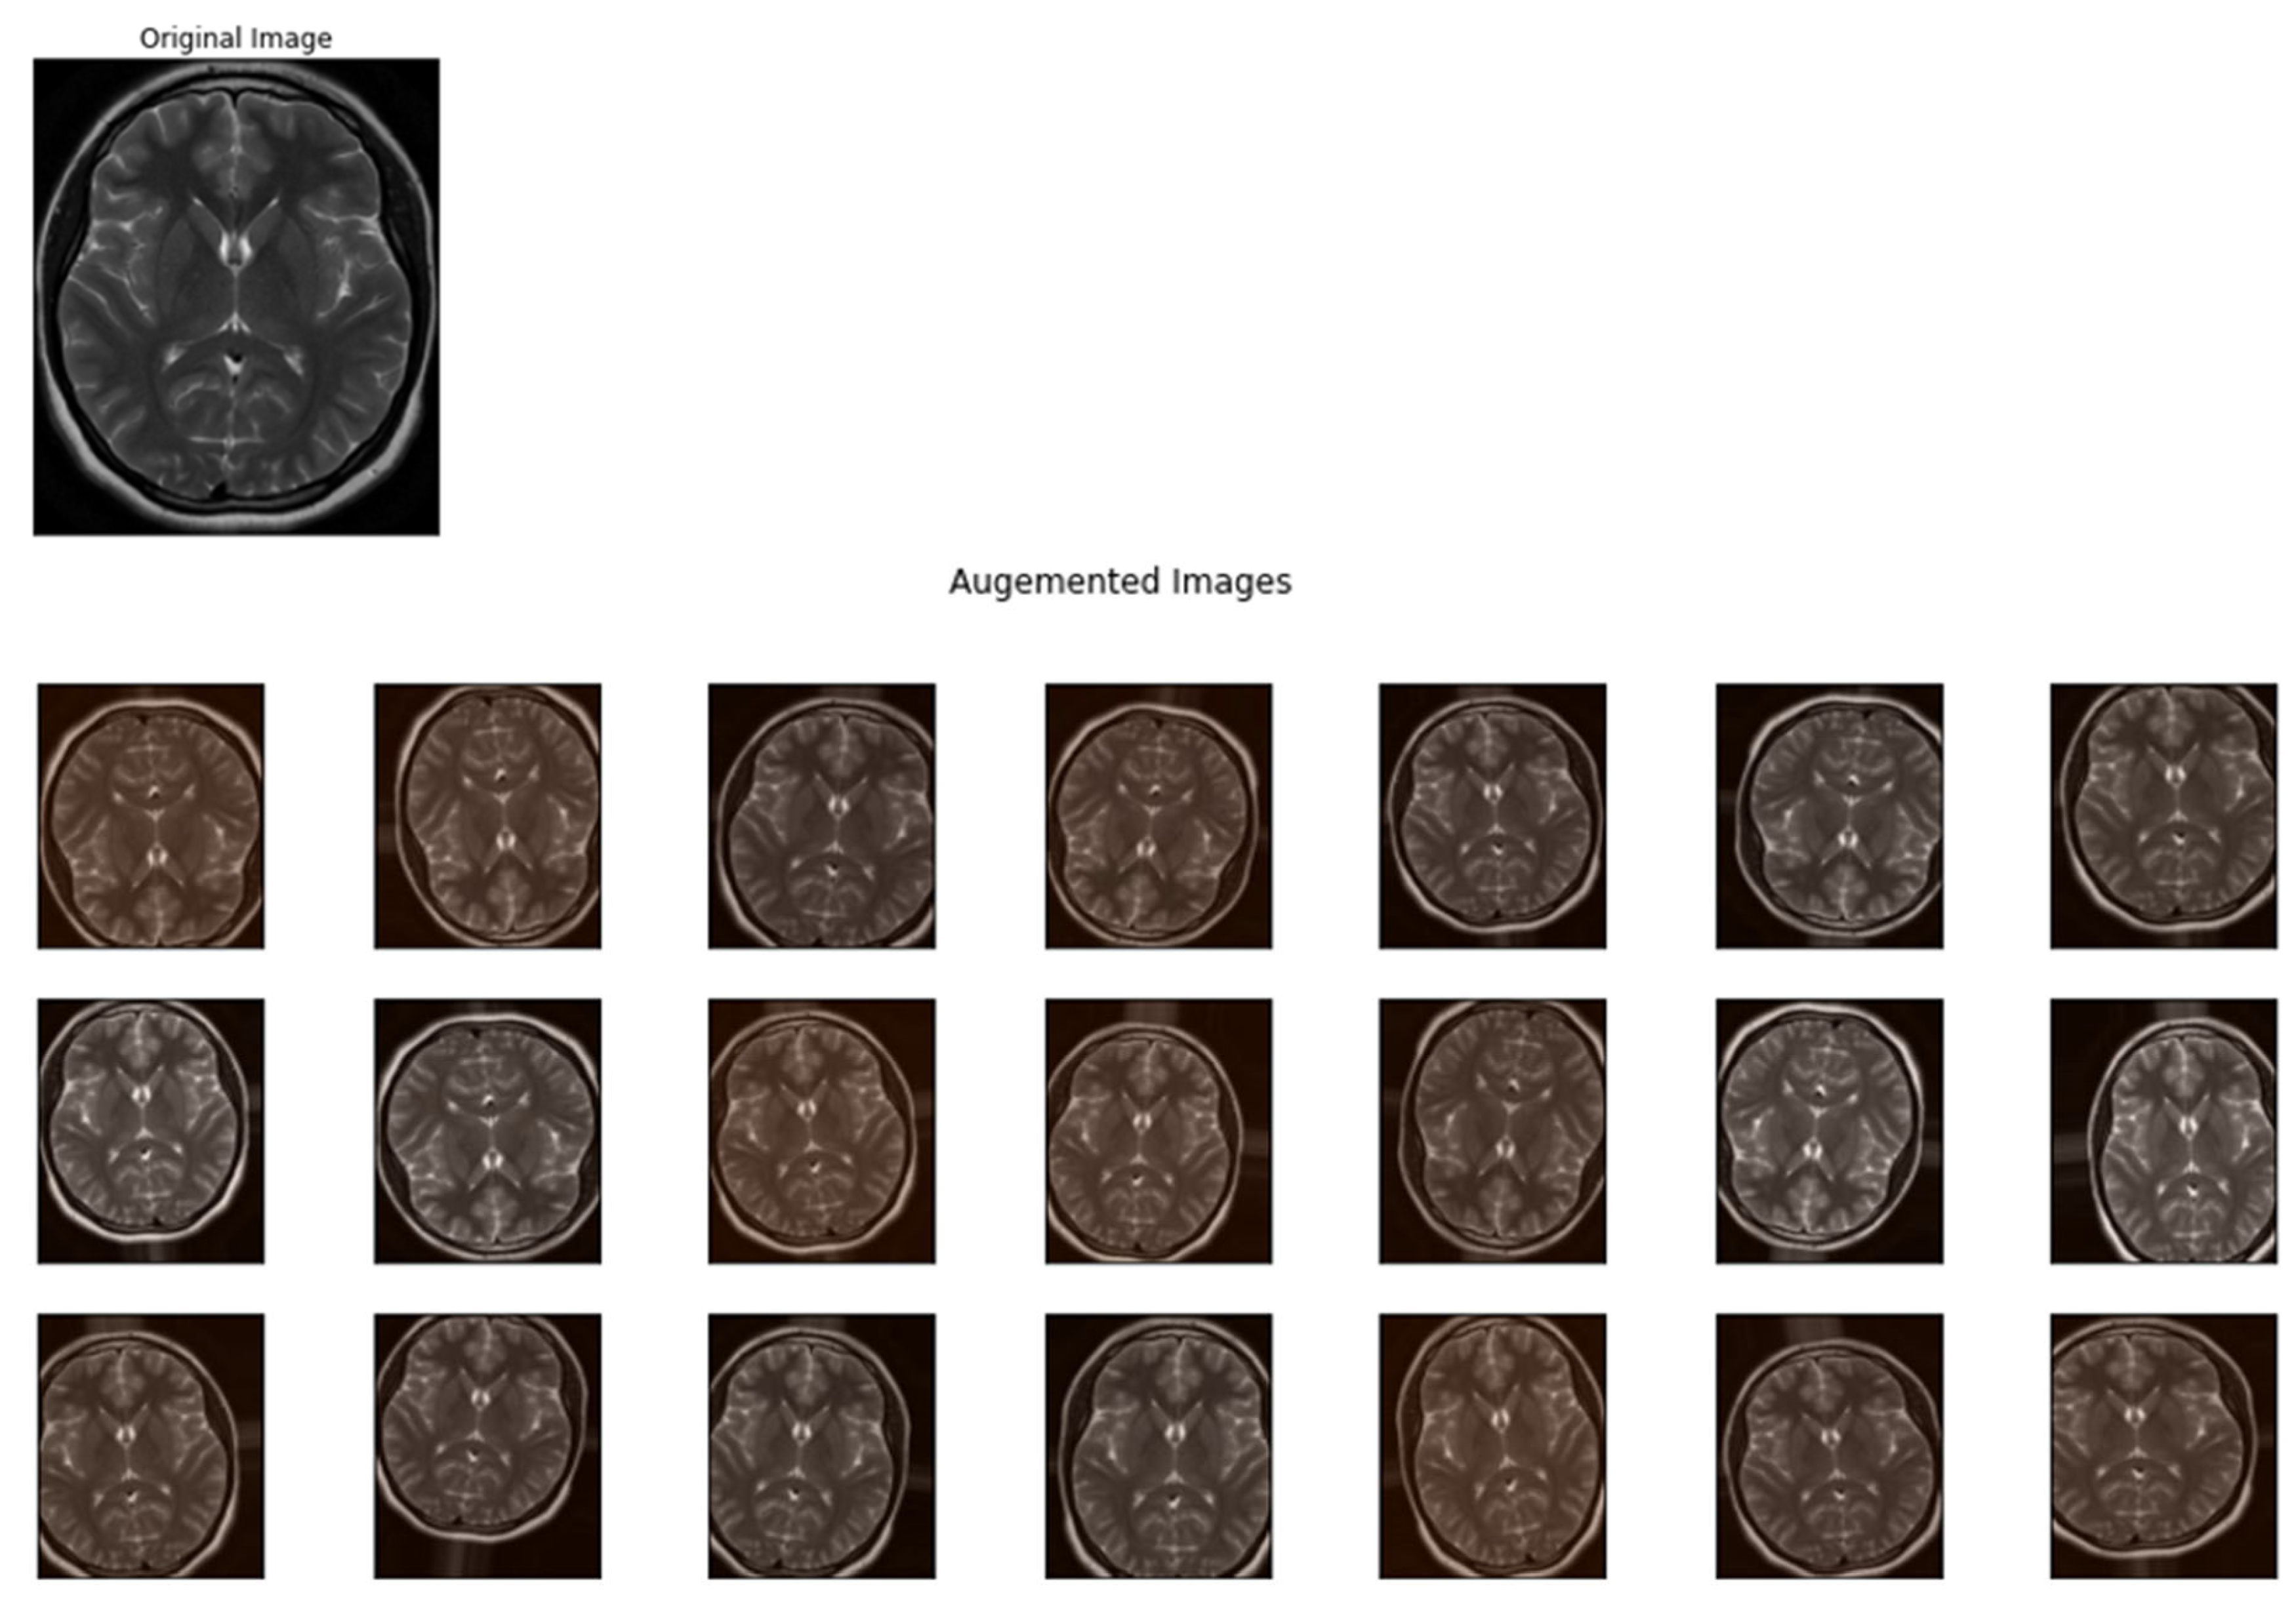

2.3. Data Augmentation

- Mitigates Overfitting: Augmentation spreads the variety of the training samples, which helps in preventing the model from memorizing specific images and overfitting.

- Improves Generalization: By simulating various scenarios, data augmentation allows the model to generalize better to new, unseen data.

- Compensates for Imbalanced Datasets: In cases where some classes are underrepresented, augmentation can help to balance the samples without the need to collect more data.

- Enhances Model Robustness: Augmented data aids the model to learn more robust features that are invariant to certain transformations, which is significant for real-world applications.